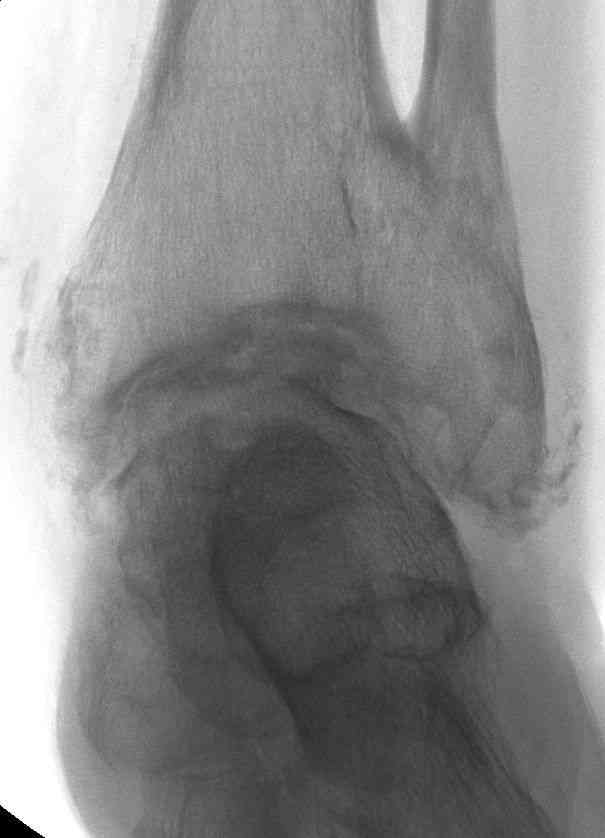

Эндопротезирование или артродезирование ?К нам обратился пациент 73 лет с жалобами на боли и деформацию в области левого голеностопного сустава. В анамнезе: в 1980 году перелом обеих лодыжек с вывихом стопы кнаружи. Лечился консервативно: одномоментная репозиция переломовывиха в левом голеностопном суставе с трансартикулярной фиксацией голеностопного сустава спицами Киршнера через пяточную, таранную, большеберцовую кости. Накладывалась гипсовая иммобилизация. Даная манипуляция осложнилась нагноением с развитием гнойного артрита. Были удалены спицы, сустав со слов больного, промывался растворами, но не вскрывался, получал антибиотики. Гнойный процесс был купирован, и рецидива с тех пор не было.Об-но: Левый голеностопный сустав деформирован за счет разрастания костной ткани и отечности мягких тканей. Левая стопа с вальгусной установкой, практически отсутствуют все своды левой стопы (стопа плоская). Полный объем движений в левом голеностопном суставе максимум достигает 15 гр, движения стопы в основном за счет подтарнного сустава. Пальпаторно область голеностопного сустава не столь болезненна, как болезненна область подтаранного сустава и область таранно-ладьевидного сустава.После изучения объективного статуса, анамнеза, рентгенснимков, больному предложен был трехсуставной артродез, так-как мы сочли это наиболее приемлемым в данном случае. Но больной отказывается от данной операции и настаивает на эндопротезировании левого голеностопного сустава. Во первых, наше отделение не имеет опыта в эндопротезиовании голеностопного сустава. Во вторых, нам кажется, что трехсуставное артродезирование в данном случае наиболее подходящее. Причиной тому, на наш взгляд, выраженная деформация левой таранной кости, как следствие аваскулярного некроза, и то что болит не голеностопный сустав в данном случае ( хотя в нем и ограничено движение), а подтранный и таранно-ладьевидный суставы и то что эндопротезирование одного голеностопного сустава не решит проблем в подтаранном, ладьевидно-таранном сочленениях. Наши доводы оказались безуспешными, а так как пациент является ученным, требовал доказательной базы наших умозаключений. Ваше мнение по данному случаю, и мы были бы благодарны, если у кого то есть материал по данной теме или есть ссылки. Заранее благодарны всем, кто примет участие в обсуждении данной темы.

По всем канонах хирургии стопы асептический некроз таранной кости - абсолютное противопоказание для эндопротезирования голеностопного сустава.